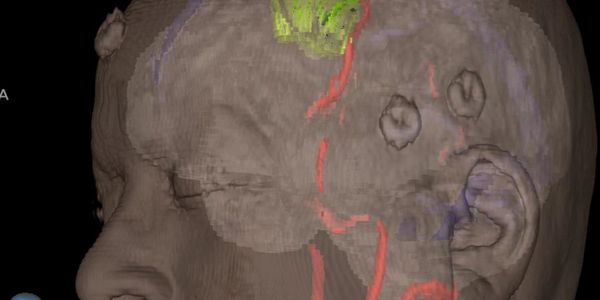

Our neurosurgeons and neurologists are nationally recognized for their expertise in addressing complex medical challenges, particularly in the treatment of brain tumors, vascular issues, and generative diseases of the brain. You can explore hundreds of video presentations of brain surgeries performed by one of our skilled neurosurgeons, Dr. Limonadi, on the YouTube channel Microneurosurgery.Org. This channel is one of the most educational and popular free online neurosurgery programs, inspiring many young minds worldwide to pursue a career in neurosciences, including spine treatment.

Andy Alvillar describes his complex brain surgery performed by physician leader, Dr. Farhad Limonadi from Lucent Neuroscience Institute.